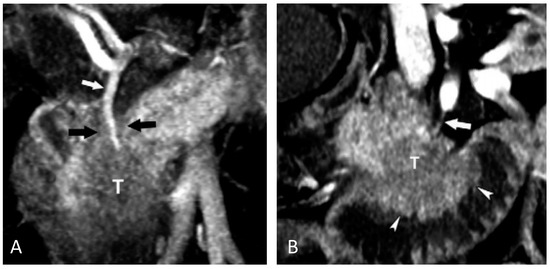

- Ahn, S.S.; Kim, M.-J.; Choi, J.-Y.; Hong, H.-S.; Chung, Y.E.; Lim, J.S. Indicative findings of pancreatic cacner in prediagnostic CT. Eur. Radiol. 2009, 19, 2448–2455. [Google Scholar] [CrossRef] [PubMed]

- Laeseke, P.F.; Chen, R.; Jeffrey, R.B.; Brentnall, T.A.; Willmann, J.K. Combining in vitro diagnostics with in vivo imaging for earlier detection of pancreatic ductal adenocarcinoma: Challenges and solutions. Radiology 2015, 277, 644–661. [Google Scholar] [CrossRef] [PubMed]